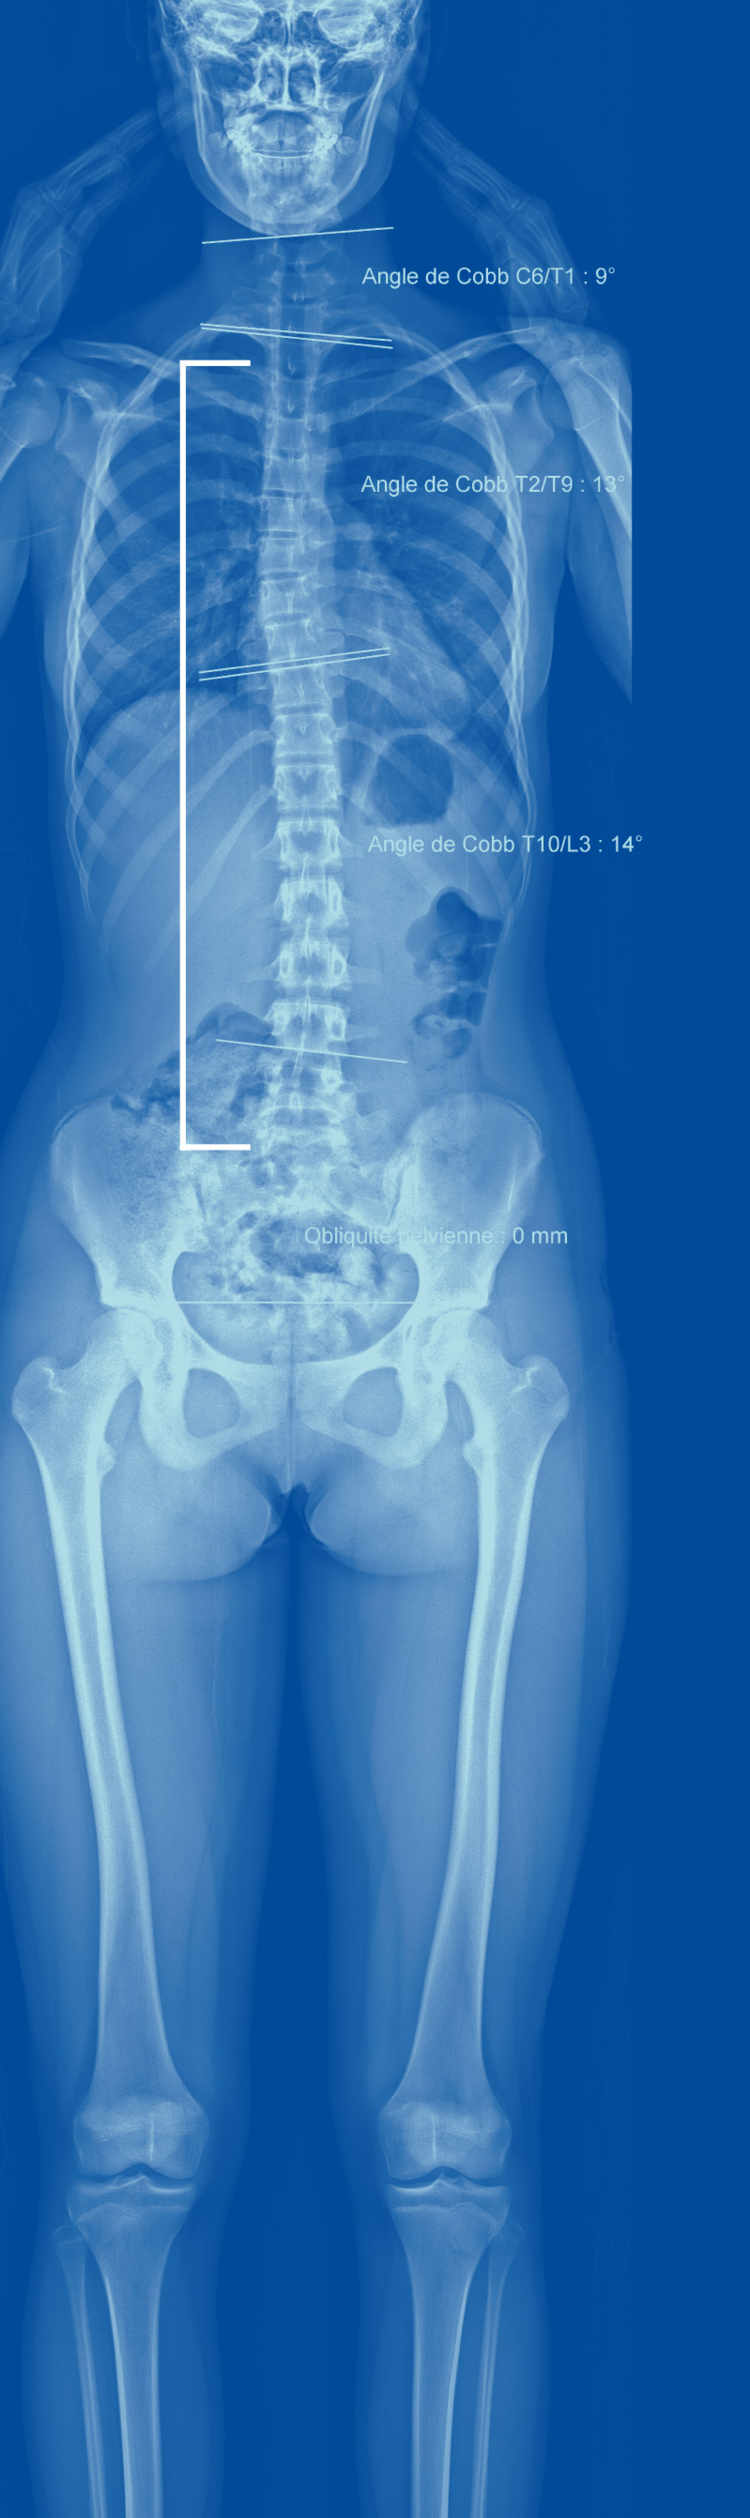

Un outil précieux pour comprendre et soigner les maux de dos, c'est ce qu'offre l'EOS, un appareil d'imagerie installé à la clinique de La Source à Lausanne depuis le printemps 2015. La technique? La radiographie classique à rayons X, mais dopée par l'informatique et des détecteurs ultraperfectionnés. L'EOS se présente comme une cabine où l'on se tient debout. Deux émetteurs de rayons X, montés sur des rails verticaux, sont cachés dans ses parois. Ils sont disposés à angle droit, ce qui permet de prendre simultanément des images de face et de profil. En face d'eux, toujours dans les parois, on trouve les détecteurs, mais au lieu de plaques photographiques que viendraient frapper les rayons X, l’appareil utilise des chambres à fil, un dispositif hyperprécis inventé par le prix Nobel Georges Charpak (1924-2010) et utilisé à l’origine en physique des particules.

«Au signal, ne plus bouger…» En 20 à 25 secondes, les images sont produites. Elles présentent plusieurs avantages. Elles sont d'abord plus précises qu'une radio du dos classique. Pourquoi? Parce qu’une radio classique de toute la colonne est en fait l’addition de trois clichés différents que l'on «scotche» ensemble. Or, ce processus induit des imprécisions importantes. Dans l'EOS, au contraire, on réalise quelques dizaines de clichés, tous aussi précis les uns que les autres, que l'ordinateur va ensuite reconstituer en une seule image. L'EOS, malgré cela, expose à 10 à 100 fois moins de radiations que la radiographie classique car ses détecteurs sont beaucoup plus sensibles. Une caractéristique très importante, en particulier pour le suivi de scolioses chez les enfants qu’il faut éviter d’irradier inutilement.

Mais l'EOS présente aussi des avantages par rapport à l'IRM et au scanner, explique Duccio Boscherini, neurochirurgien à La Source. Ces deux dispositifs fournissent en effet des images de la colonne, mais pas du reste du corps, contrairement à l’EOS. Or, les genoux ou les hanches peuvent être la cause de déséquilibres créant des maux de dos. De même, scanner et IRM sont réalisés quand la personne est couchée. «Ils fournissent donc des images restreintes de l'anatomie, dans une position statique et non physiologique.» Par opposition, l'EOS montre toute la personne en position debout.

Les médecins se rendent compte que les maux de dos doivent être évalués de manière globale, qu'ils sont le résultat d'une interaction subtile entre la posture de la personne, sa musculature et des caractéristiques anatomiques qui lui sont propres. «Il existe un cône d'économie en position debout, relate le chirurgien, un ensemble de postures possibles où la musculature est sollicitée au minimum.» Quand on s'en écarte, celle-ci doit travailler davantage, ce qui augmente le risque de maux de dos.

On a désormais identifié des paramètres normaux, poursuit le chirurgien, des angles (de cambrure par exemple) ou des mesures (l'emplacement du centre de gravité) qui permettent de prédire si une personne risque davantage de connaître des maux de dos. Telle patiente, par exemple, a un sacrum presque à l'horizontale, illustre le spécialiste: c'est très rare et cela cause naturellement une cambrure exagérée qui explique ses maux de dos.

Ces valeurs, l'EOS les calcule aisément et les fournit rapidement. Une fois munis de ces données, les spécialistes comprennent mieux l'origine des maux de dos. Ces mesures sont également précieuses pour déterminer où opérer pour être le plus efficace, de même que pour évaluer comment la colonne s'est repositionnée après une opération.